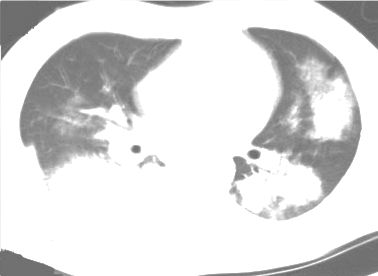

The evaluation of infectious disease processes on radiologic images is an important and challenging task in medical image analysis. Pulmonary infections can often be best imaged and evaluated through computed tomography (CT) scans, which are often not available in low-resource environments and difficult to obtain for critically ill patients. On the other hand, X-ray, a different type of imaging procedure, is inexpensive, often available at the bedside and more widely available, but offers a simpler, two dimensional image. We show that by relying on a model that learns to generate CT images from X-rays synthetically, we can improve the automatic disease classification accuracy and provide clinicians with a different look at the pulmonary disease process. Specifically, we investigate Tuberculosis (TB), a deadly bacterial infectious disease that predominantly affects the lungs, but also other organ systems. We show that relying on synthetically generated CT improves TB identification by 7.50% and distinguishes TB properties up to 12.16% better than the X-ray baseline.